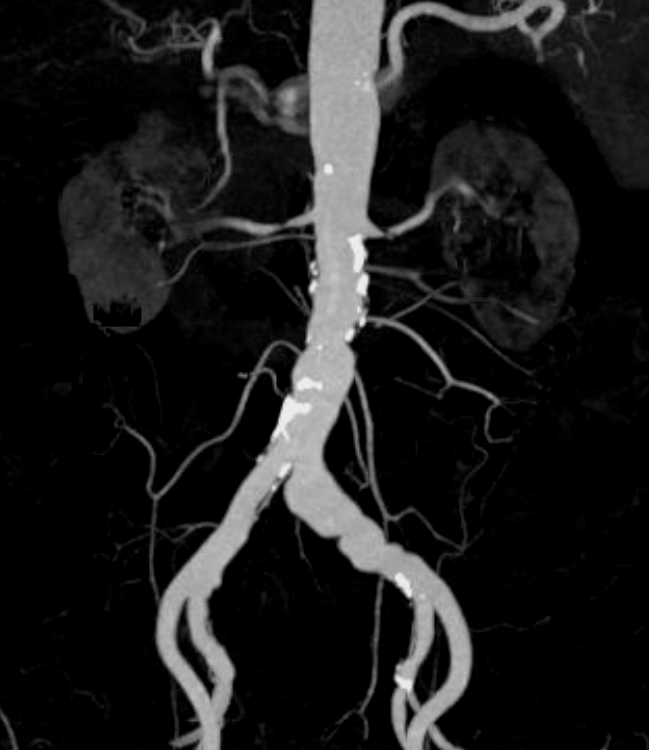

现病史:患者3年前体检发现血肌酐升高,半年前就诊肾内科,检查发现双侧肾动脉狭窄,血肌酐141μmol/L,就诊我科门诊,CTA提示:双肾动脉近段重度狭窄。现为进一步诊治收入我科。

肾动脉CTA:双侧可见副肾动脉,双肾动脉起始部可见钙化斑块,双侧肾动脉及左侧副肾动脉近段重度狭窄。左髂总动脉夹层。

局麻后穿刺右股总动脉并置入7F血管鞘。腹主动脉造影示:腹主动脉管腔不光滑,左侧髂总动脉管腔增粗,双侧肾动脉管腔重度狭窄,右侧可见副肾动脉,左侧副肾动脉显示不清。